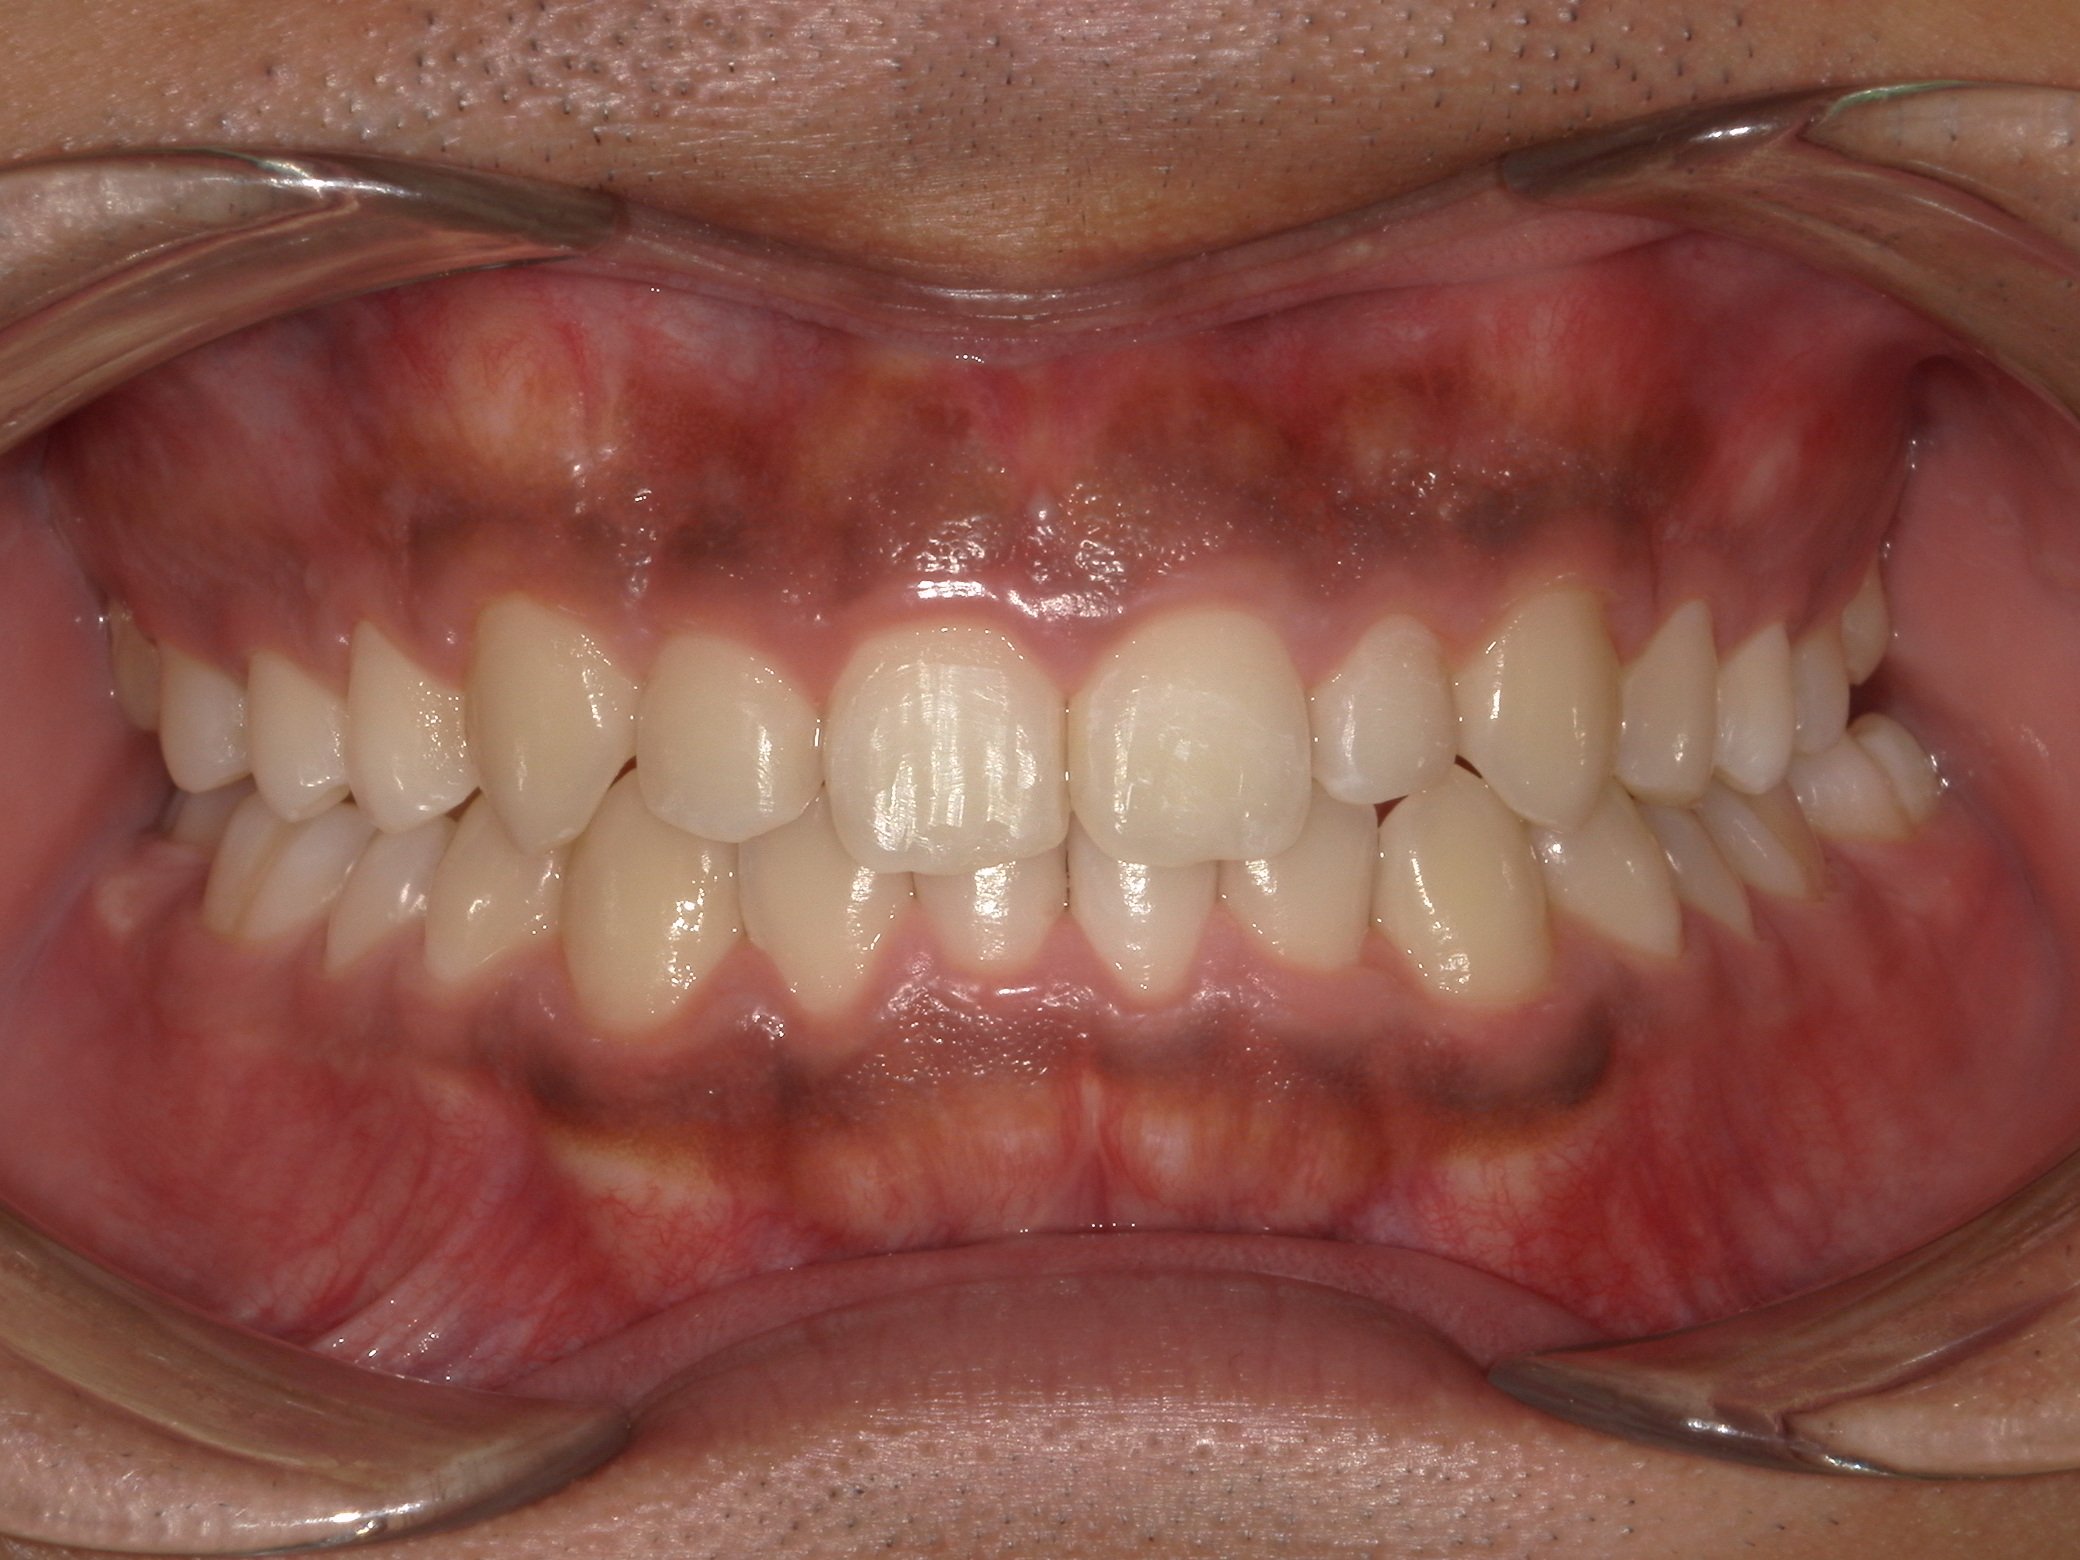

After

(治療後)

患者様情報 19歳 男性 診断名 叢生 治療内容 マウスピース矯正(クリアコレクト) 期間・通院回数 20か月 / 9回 費用(総額) 755,000円(税込) リスク・副作用 治療の初期段階では痛みや不快感が生じやすくなりますが、通常1週間前後で慣れていきます。 当院で行うマウスピース矯正の特徴